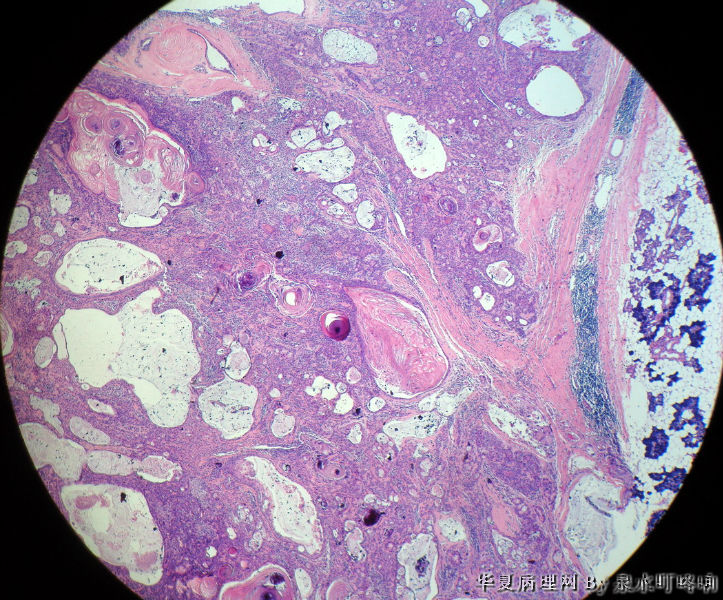

左腮腺肿物

女,38岁,左耳下方肿物,临床诊断:左腮腺肿物。

大体:灰白肿物一个,大小约4×3.5×3厘米,切面灰白,质略软,可见多发囊腔。

(左腮腺)多形性腺瘤

多形性腺瘤(粘液软骨样区域+上皮成分)

瘤组织由多种上皮成分(腺上皮+肌上皮+鳞化上皮)及黏液软骨样基质构成,多形性腺瘤可以囊性变,多结节状分布。

多形性腺瘤,肌上皮、腺上皮增生,鳞化、粘液背景

1、境界清楚

2、两种类型细胞:导管上皮+肌上皮,肌上皮与周围间质有融合现象。

3、伴有角化的鳞状分化。

4、间质:软骨粘液样间质+弹力纤维。

综上:多形性腺瘤。